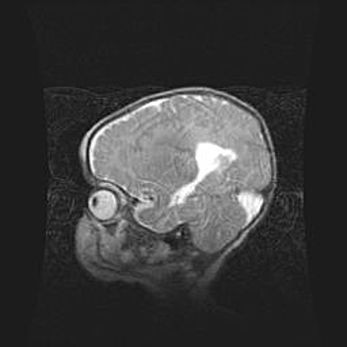

Подострая гематома правой гемисферы мозжечка.

Наружная гидроцефалия.

Возраст: 15 дней

Вес: 3100 г

Пол: женский

Окружность головы: 37 см

Срок гестации: 35-36 недель

При открытой наружной форме гидроцефалии у новорожденных расширяются и переполняются субарахноидные пространства.

Кровоизлияния в мозжечок имеют две клинико-анатомические формы: полушарные гематомы и кровоизлияния в червь.

К появлению этой патологии может привести: повреждения головного мозга, возникающие в результате асфиксии и гипоксии плода при беременности, или травмы во время родов. Редко гематома мозжечка может быть результатом первичной коагулопатии и сосудистой мальформации, диссеминированном внутрисосудистом свертывании, изоиммунной тромбоцитопении.